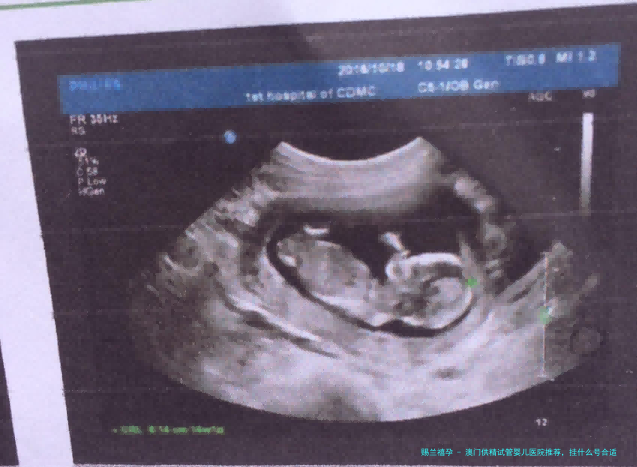

想要在澳门打开生育路程,抉择适当的试管婴儿医院非常重要。澳门特别行政区拥有众多优异的医疗机构,为寻求辅助生殖治疗的家庭提供高质量服务。本文将给您详细介绍澳门特别行政区供精试管婴儿医院保举,并剖析不同医院的特性,帮助您更全方位地认识选择根据。

在澳门,一些医院和诊所提供供精试管婴儿服务。 选择一家合适的机构不仅关系到治疗效果,也关乎您的身心健康。 以下是一些备受推崇的供精试管婴儿医院,您可以根据自身情况进行筛选: